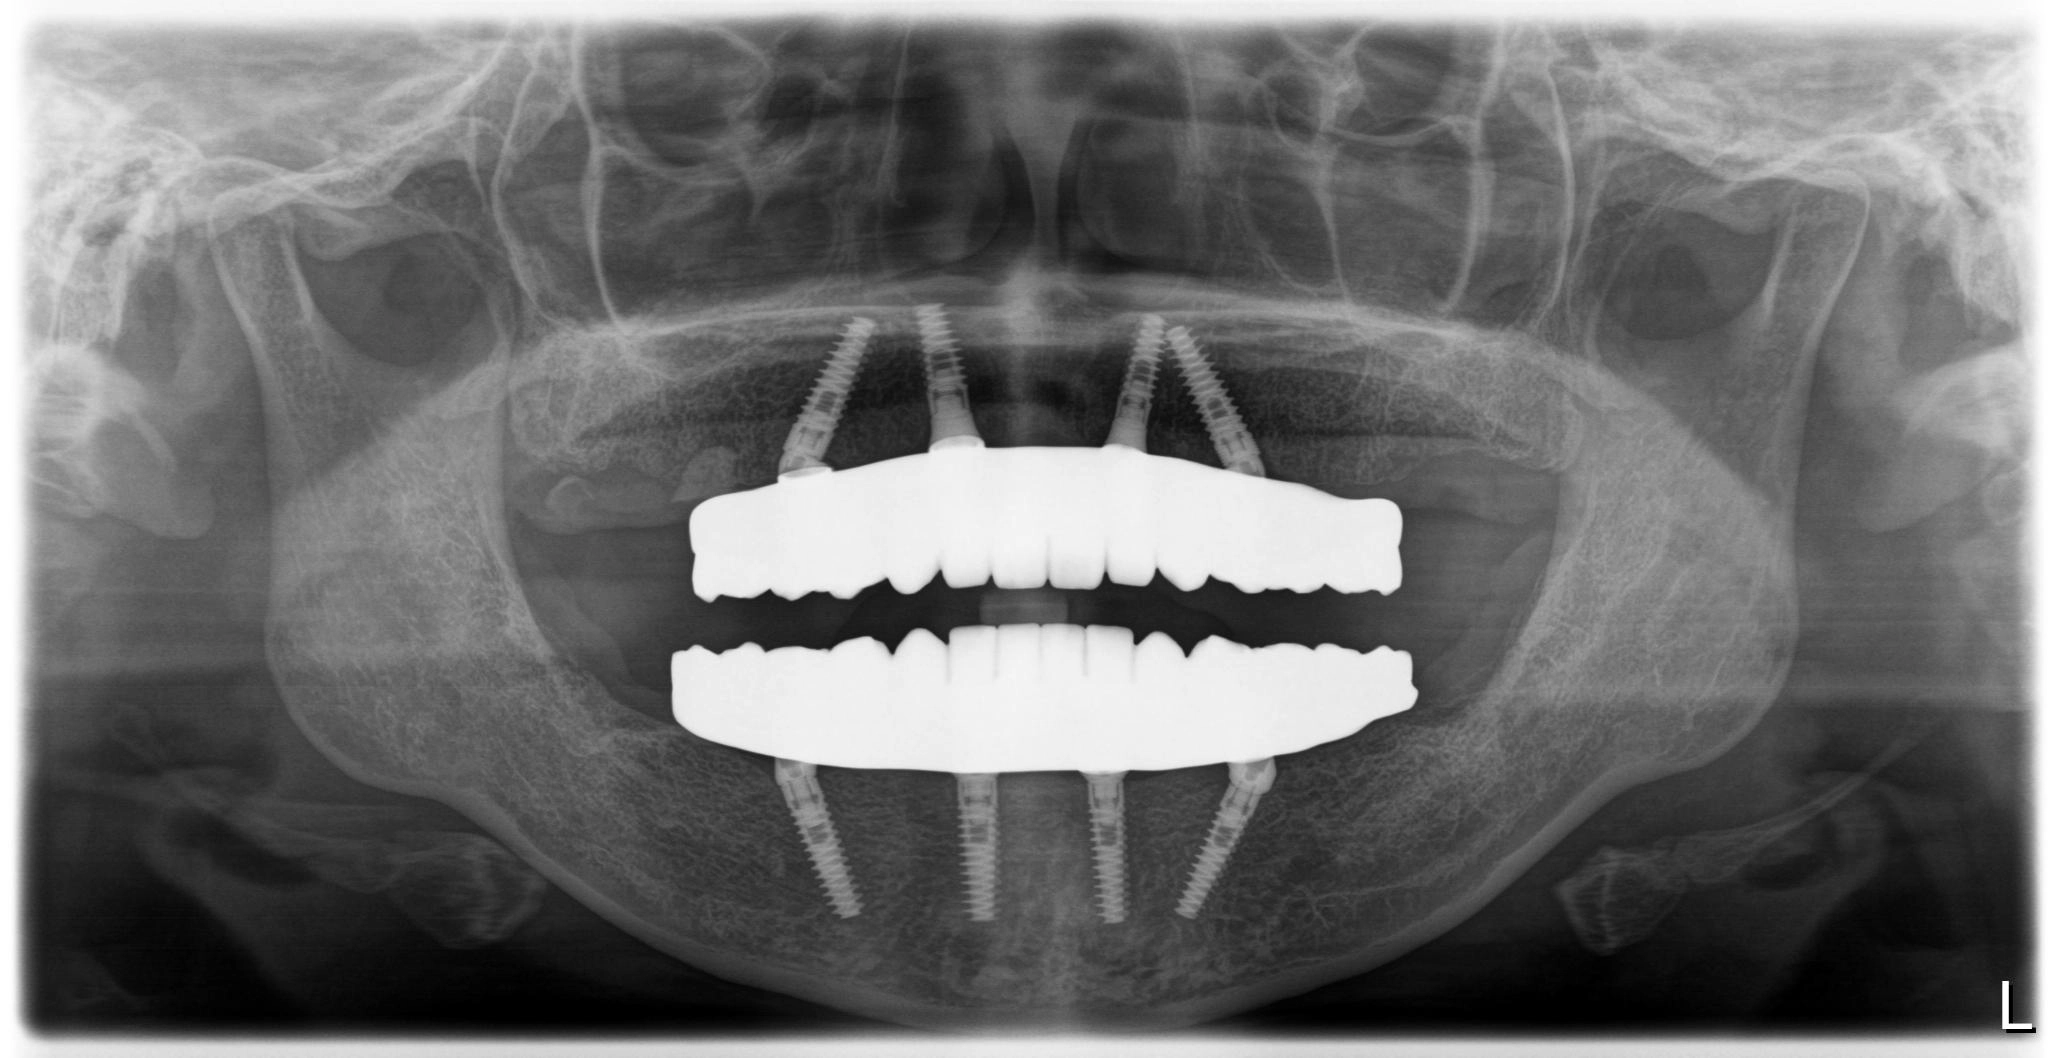

福岡県 49歳(男性)

「長年の口元の不安が負担」

術後

内容 :上下顎オールオン4ザイゴマ0

費用 :4,989,600円

※モニター価格

期間 :半年

リスク:出血・腫れ・痺れ・痛み

手術当日に歯が入り、その即時性に深く満足しています。これまでは人前で笑えないことが最大の悩みでしたが、これからは笑顔が増えていきそうです。